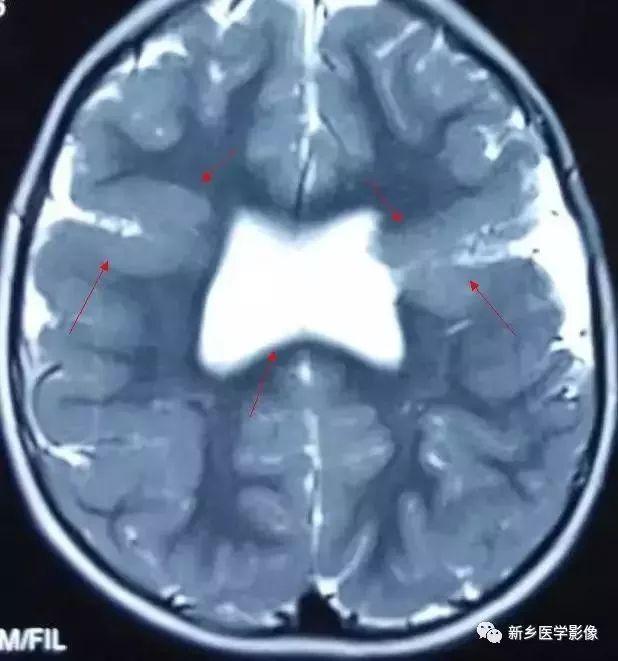

(2)脑裂畸形:胚胎期脑的发育经历6个主要阶段:①背侧诱导阶段;③腹侧诱导阶段;③神经增生阶段;④神经元移行阶段;⑤组织形成阶段;⑥髓鞘形成阶段。脑裂畸形发生在神经元移行阶段。脑裂畸形可累及一侧或双侧大脑半球,脑裂畸形位于侧面.常累及中央前、后回区偶尔位于大脑半球的其他部位。脑裂畸形的裂隙可以很窄,裂隙两侧灰质紧密相贴,称闭合型。裂隙也可以很宽,中间为脑脊液,分离型。

分离型脑裂畸形需要与脑穿通畸形囊肿鉴别.脑裂畸形的裂隙两旁一定为一灰质结构,而脑穿通畸形囊肿周围无脑灰质包绕。裂隙两旁是否为灰质结构是区别脑裂畸形与脑穿通畸形囊肿的可靠征象。裂隙两侧的灰质可不正常,可呈多小脑回样。脑裂畸形也可合并脑灰质异位。

分离型在CT很容易显示.闭合型有时容易漏诊.MRI对裂隙两侧的灰质结构容易辨认。脑裂畸形常合并透明隔缺如.侧脑室扩大,脑裂畸形处脑室边缘不规则.常可见指向裂隙的裂或 三角形憩室存在。

临床上脑裂畸形常表现有癫痫发作,其他神经系统症状可从很轻微到很严重.主要取决于脑裂畸形使脑组织缺损的严重程度。单侧闭合型脑裂畸形症状通常较轻,双侧分离型脑裂畸形症状较明显。